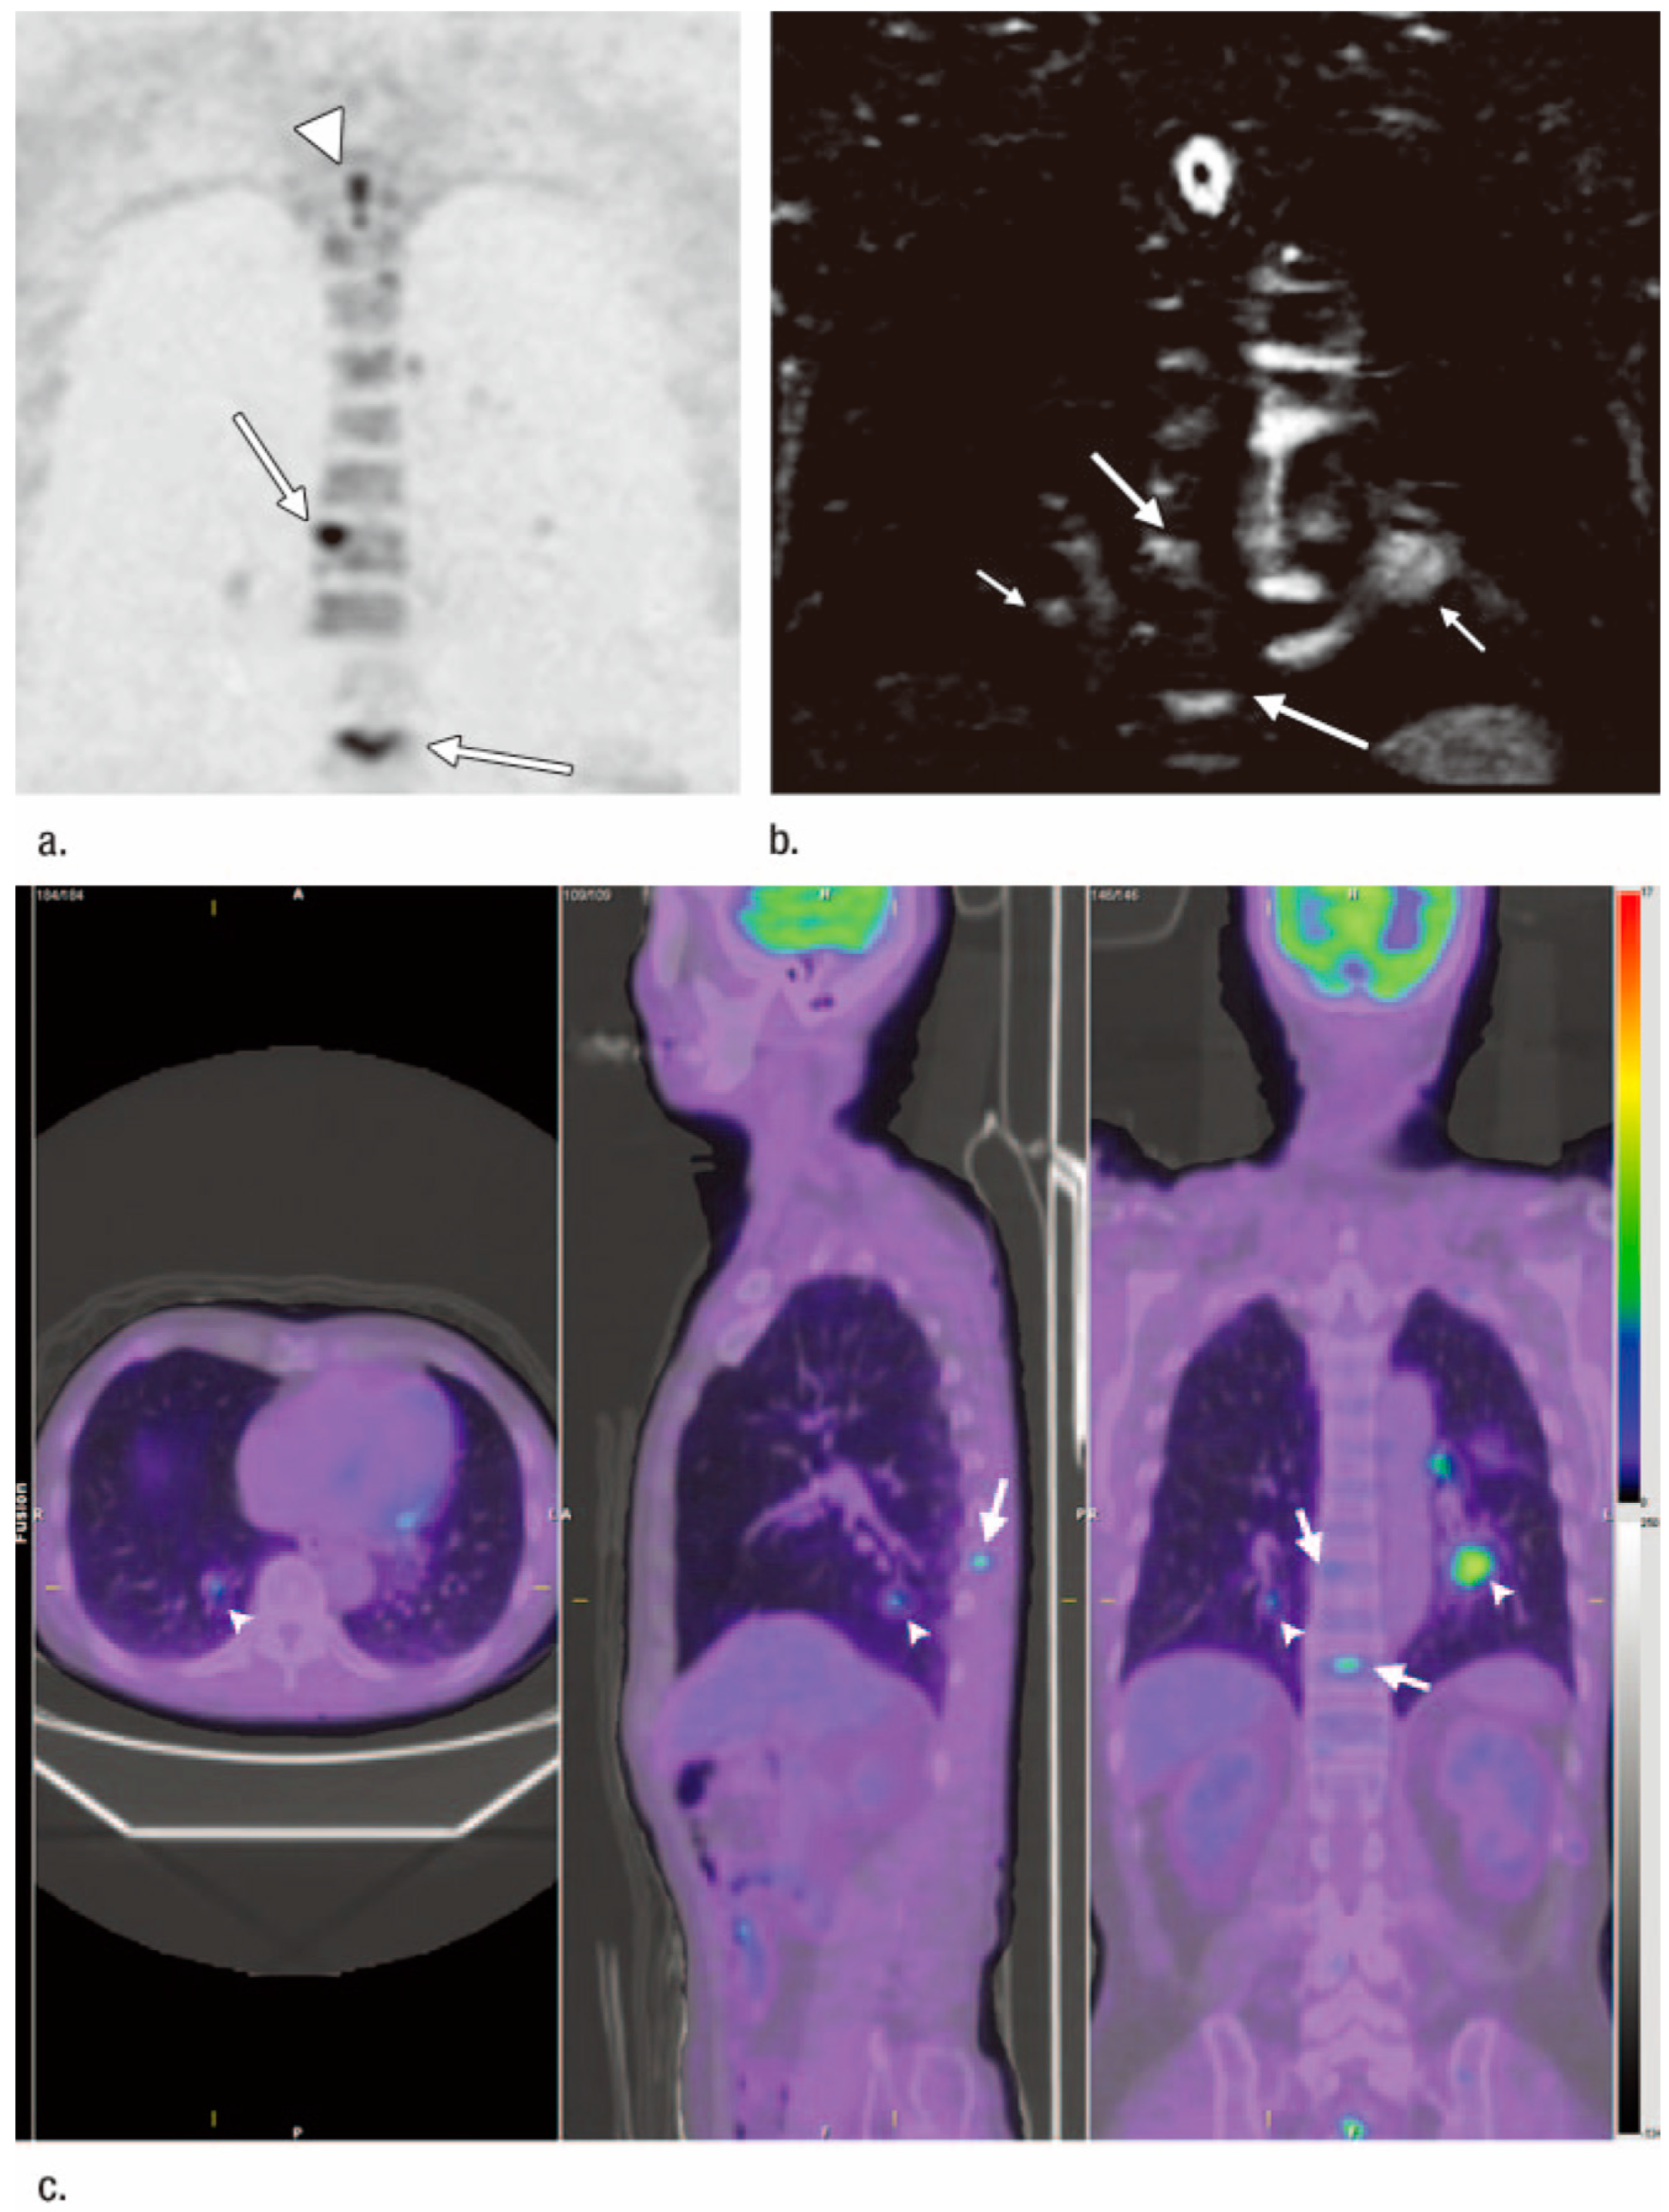

- Ohno, Y.; Koyama, H.; Yoshikawa, T.; Takenaka, D.; Seki, S.; Yui, M.; Yamagata, H.; Aoyagi, K.; Matsumoto, S.; Sugimura, K. Three-way Comparison of Whole-Body MR, Coregistered Whole-Body FDG PET/MR, and Integrated Whole-Body FDG PET/CT Imaging: TNM and Stage Assessment Capability for Non-Small Cell Lung Cancer Patients. Radiology 2015, 275, 849–861. [Google Scholar] [CrossRef]

- Ohno, Y.; Yoshikawa, T.; Kishida, Y.; Seki, S.; Koyama, H.; Yui, M.; Kassai, Y.; Aoyagi, K.; Kaminaga, S.; Sugimura, K. Diagnostic performance of different imaging modalities in the assessment of distant metastasis and local recurrence of tumor in patients with non-small cell lung cancer. J. Magn. Reson. Imaging 2017, 46, 1707–1717. [Google Scholar] [CrossRef] [PubMed]

- Ohno, Y.; Takeshi, Y.; Takenaka, D.; Koyama, H.; Aoyagi, K.; Yui, M. Comparison of Diagnostic Accuracy for TNM Stage Among Whole-Body MRI and Coregistered PET/MRI Using 1.5-T and 3-T MRI Systems and Integrated PET/CT for Non-Small Cell Lung Cancer. AJR Am. J. Roentgenol. 2020, 215, 1191–1198. [Google Scholar] [CrossRef] [PubMed]